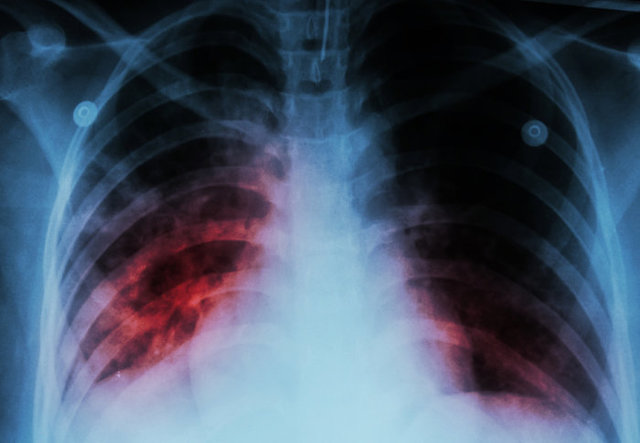

معاون آموزشی بیمارستان مسیح دانشوری در ادامه با اشاره به برخی راههای تشخیص بیمار مسلول، اظهار کرد: بیماران مسلول افرادی هستند با علائم سرفه بیش از ۲ هفته خلط خونی، تعریق شبانه، کاهش وزن، تب طولانی و ... که باید حتما بررسی شوند. راه عمده شناسایی سل ریوی انجام آزمون اسمیر و کشت خلط از نظر میکروب بیماری سل است و این آزمایش در اکثر آزمایشگاهها و مراکز بهداشتی انجام میشود.